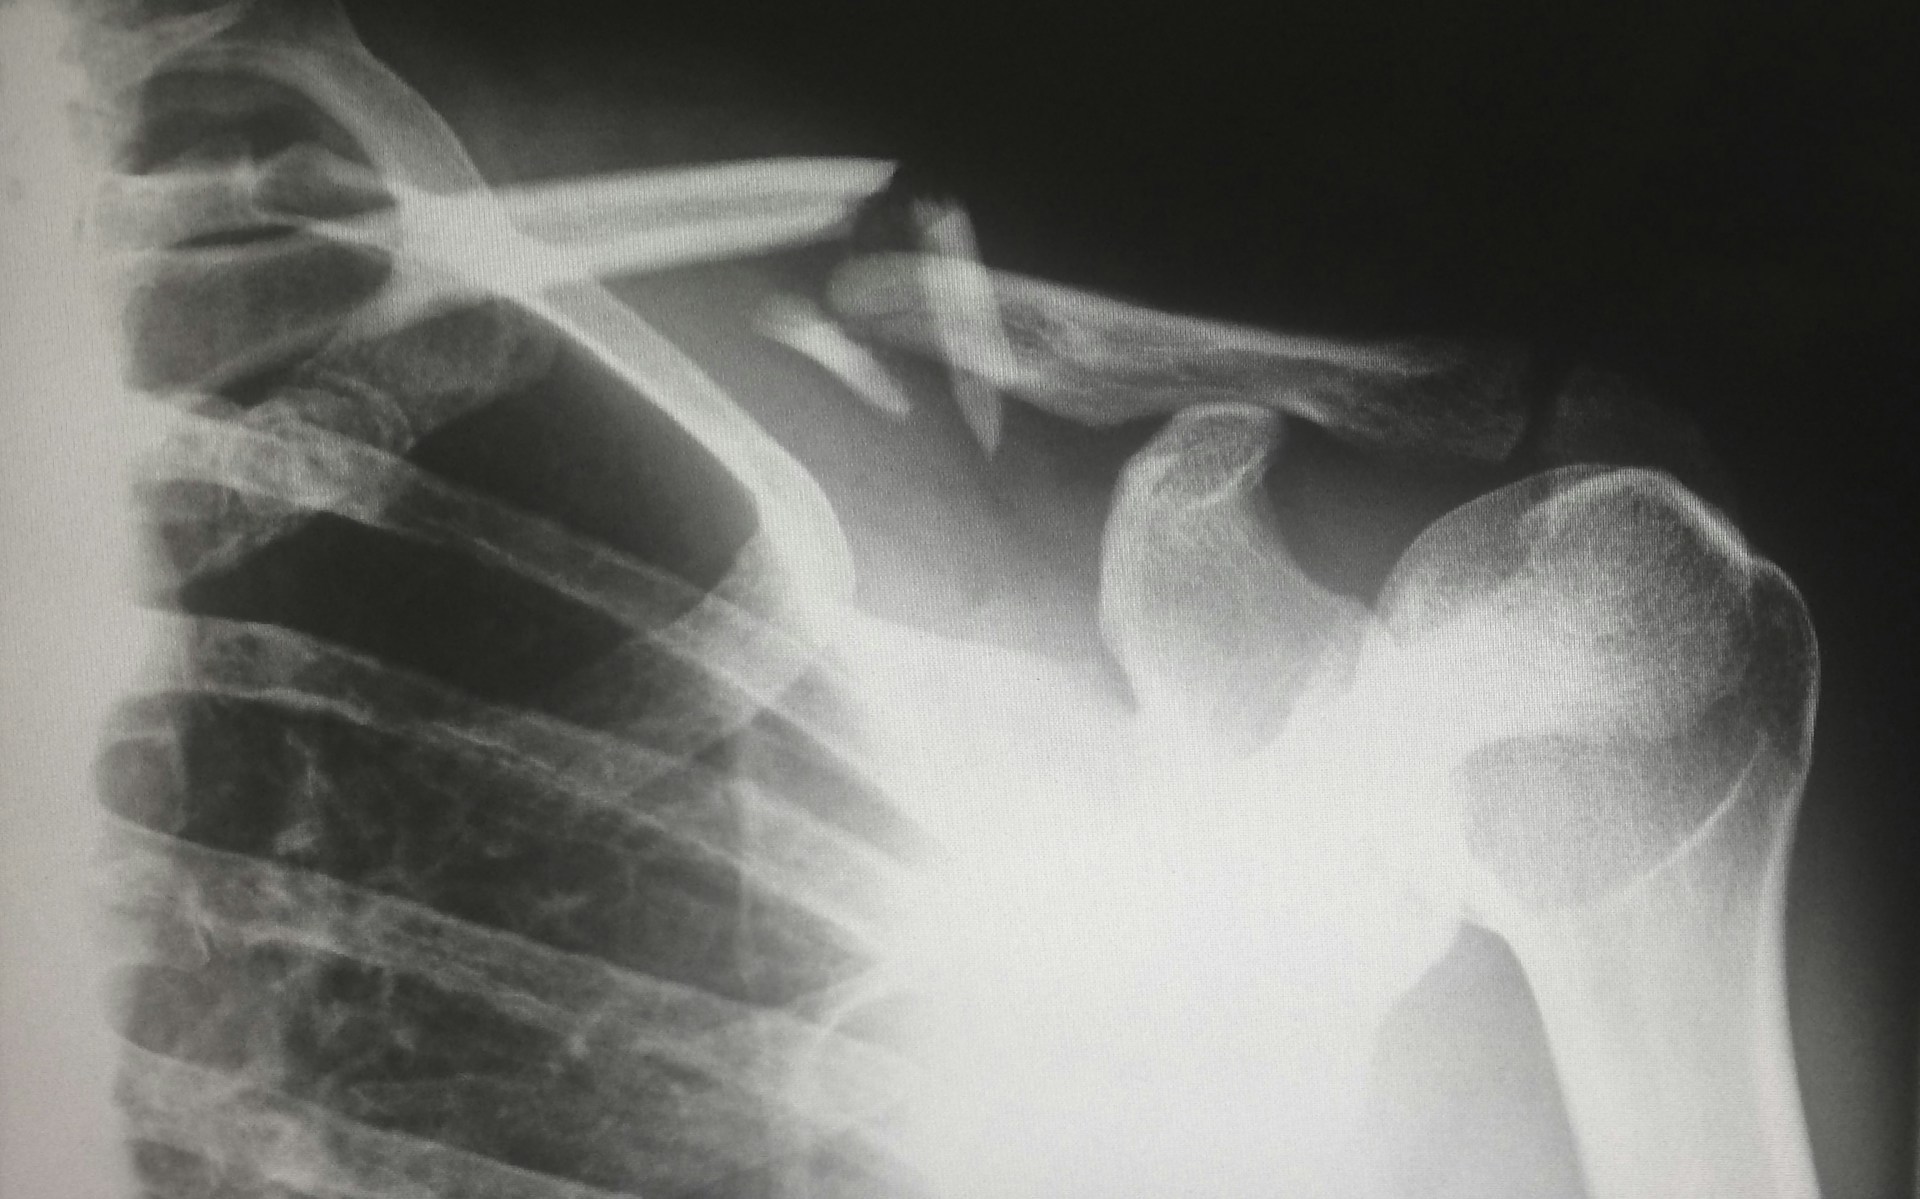

Здоровье, новостиКитайские учёные создали «костный клей», который сращивает переломы за 3 минуты

Так, в клиническом случае с переломом запястья пациенту сделали всего 3-сантиметровый разрез и ввели препарат. Уже через три минуты кость была зафиксирована, а через три месяца проверка показала полное заживление без осложнений.